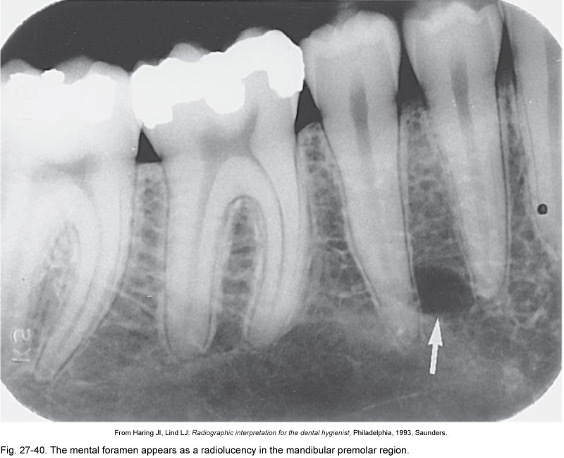

What is this a picture of and what is it? What is an example?

A

Foramen- Opening or hole in bone, nerves, blood vessels pass through

eg. mental foramen